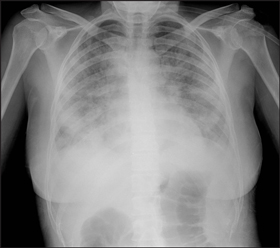

Chest x-rays were taken of 59 of the 64 patients, and abnormalities were detected in 31 patients. Abnormal radiological features ranged from localised infiltrates to bilateral airspace consolidation (Box 4). Four patients had radiological abnormalities attributable to chronic lung conditions without evidence of concurrent pneumonia.

4 Chest x-rays showing typical abnormalities found in patients hospitalised with influenza, 17 June to 31 July 2009

Patient with seasonal influenza showing bilateral airspace opacity. |